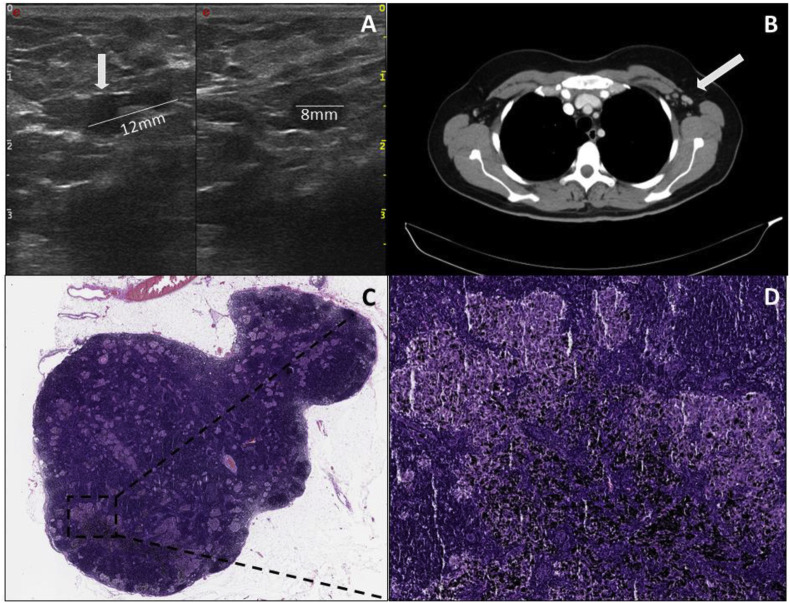

A 43-year-old woman was first diagnosed with melanoma with a tumour thickness of 1.4 mm in the left mammillary area in June 2020. Sentinel lymph node excision was performed in the left axilla, which showed a metastasis with a maximum diameter of 0.8 mm. Consecutive tumour staging by CT and magnetic resonance imaging showed no evidence of metastasis. Subsequently, with the BRAF V600E mutation present, adjuvant therapy with dabrafenib and trametinib was initiated in August 2020. On 2nd March 2021, the first vaccination and on 23rd March 2021, the second vaccination with BioNTech's vaccine took place. In late April 2021, lymph node metastases were suspected sonographically in the left axilla during tumour follow-up (Fig. 4 A). Consecutive radiologic imaging with CT scanning also revealed suspicious lymph nodes for metastasis in the left axilla (Fig. 4B). Therefore, the indication for complete lymphadenectomy was decided in the interdisciplinary tumour conference. In mid-May 2021, a complete lymph node removal of the left axilla was performed. Intraoperatively, there were several black coloured lymph nodes measuring a maximum of 1 cm. Histologically, there was no evidence of melanoma metastasis in the 15 harvested lymph nodes; instead, there were histologic signs of a sarcoid-like reaction. The black discolouration of the lymph nodes was a pigment deposit from a long-standing tattoo on the patient's left scapula (Fig. 4C and D). Postoperatively, the patient showed marked lymphorrhea, requiring multiple sclerotherapy with ethoxysclerol. The patient was hospitalised for a total of 14 days.

Fig. 4.

Case 2. (A) (Left) Ultrasound shows an enlarged lymph node with preserved vascular hilus and unilaterally widened, echo-poor margin. (Right) In the other plane, the enlarged area is echo-poor and rounded. (B) CT scan shows multiple lymph nodes suspicious for malignancy in the left axilla (

). (C) Histopathologic image of the lymph node. (D)The sarcoidosis-like granulomas/lesions are visible in addition to distinct pigmentary deposits associated with the patient's underlying tattooing.